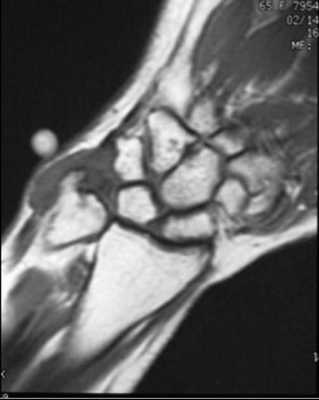

(Слева) MPT в режиме Т2*GRE, коронарный срез: по периферии ТФХК визуализируется металлический артефакт после удаления поврежденных тканей. Следует отметить измененный контур центральной части.

(Справа) Непрямая МР-артрография в режиме Т1ВИ FS с КУ, коронарный срез: определяется интактный восстановленный участок ТФХК. На его периферии визуализируется металлический артефакт. Усиление интенсивности сигнала от ТФХК укладывается в рамки ожидаемого после операции. Контрастирование собственной жидкости во всех суставах обусловлено экскрецией контрастного препарата синовиальной оболочкой, что патологией не является.